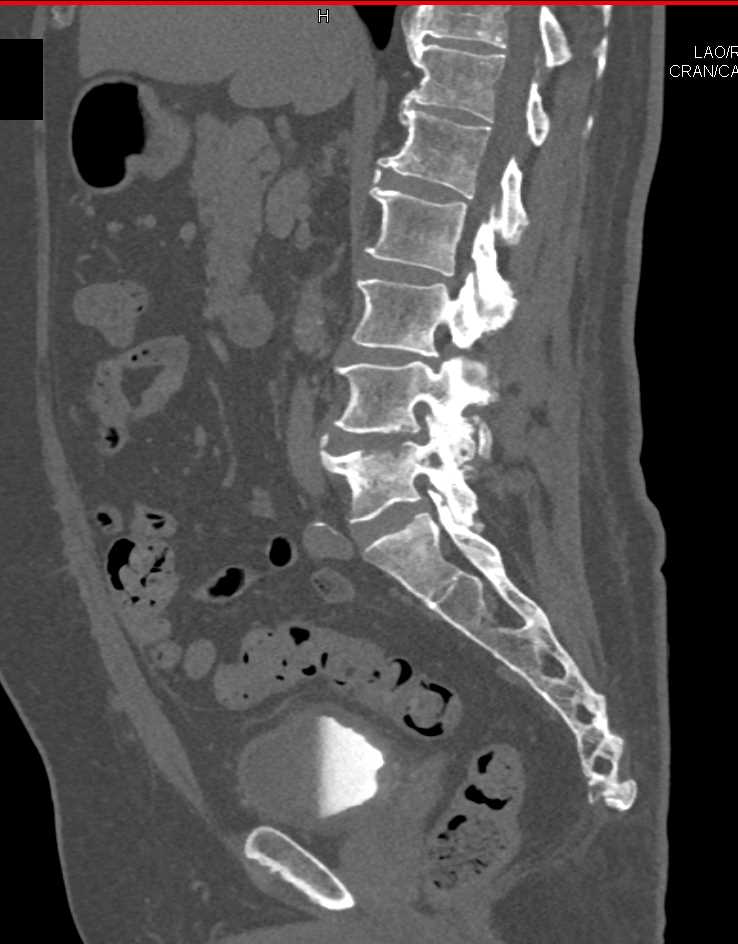

Infection at L4-L5 interspace